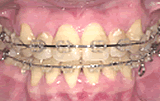

症例2/歯並びがでこぼこしている

【歯科手術中】

(器具を取り付けた状態)